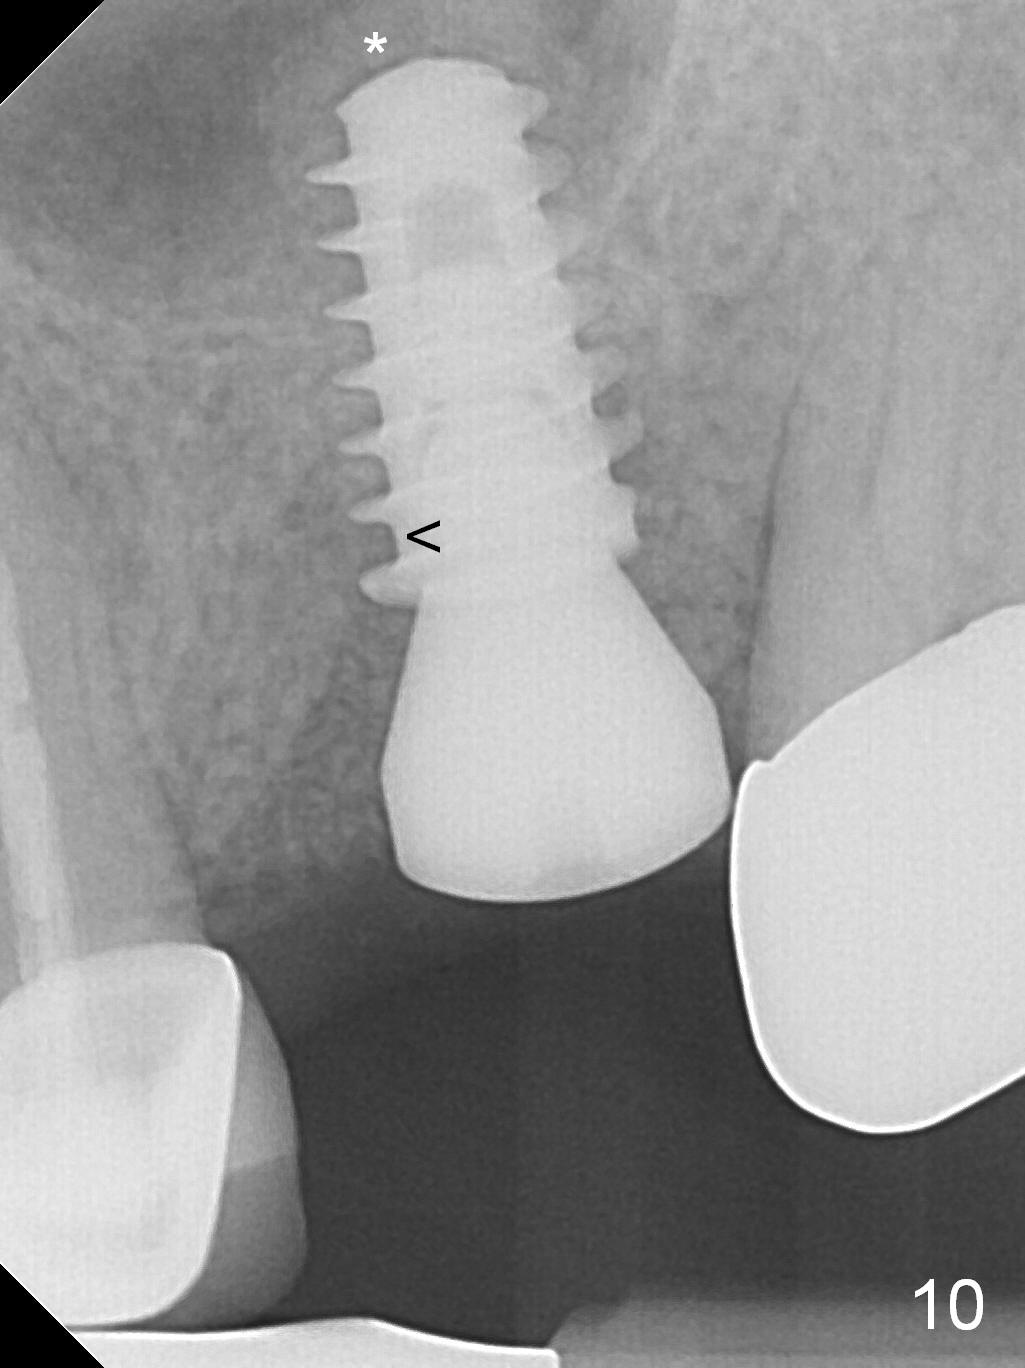

The patient is doing well 9 days postop. The immediate provisional is loose and over-sized. It is removed for trimming and reline; the socket and bone graft (Fig.8 *) are healing. It appears that an angled abutment is required next time of provisional revision. When an angled abutment is being placed 23 days postop (Fig.9), it appears to wiggle the implant due to its long leverage. Instead a healing abutment is placed. The implant is unstable 4.5 months postop with seemingly excessive bone-implant gap (Fig.10 <). The 5.5x9 mm implant is removed. A 5x17 mm tap is used to change the trajectory and sinus lift, followed by 6x17 one (Fig.11). Finally a 6x14 mm tissue-level implant is placed with insertion torque > 50 Ncm (Fig.12; vs. <20 Ncm (Fig.7,10)) and improved trajectory. An immediate provisional is fabricated to prevent the mesial drifting of the tooth #15 (Fig.13 P (*: occlusal clearance)). By using the taps and placing the longer implant, the sinus lift is more obvious (compare Fig.10 and 12 (*)). Sinus lift remains evident 3.5 months postop (Fig.14) with apparently osteointegration (Fig.15).